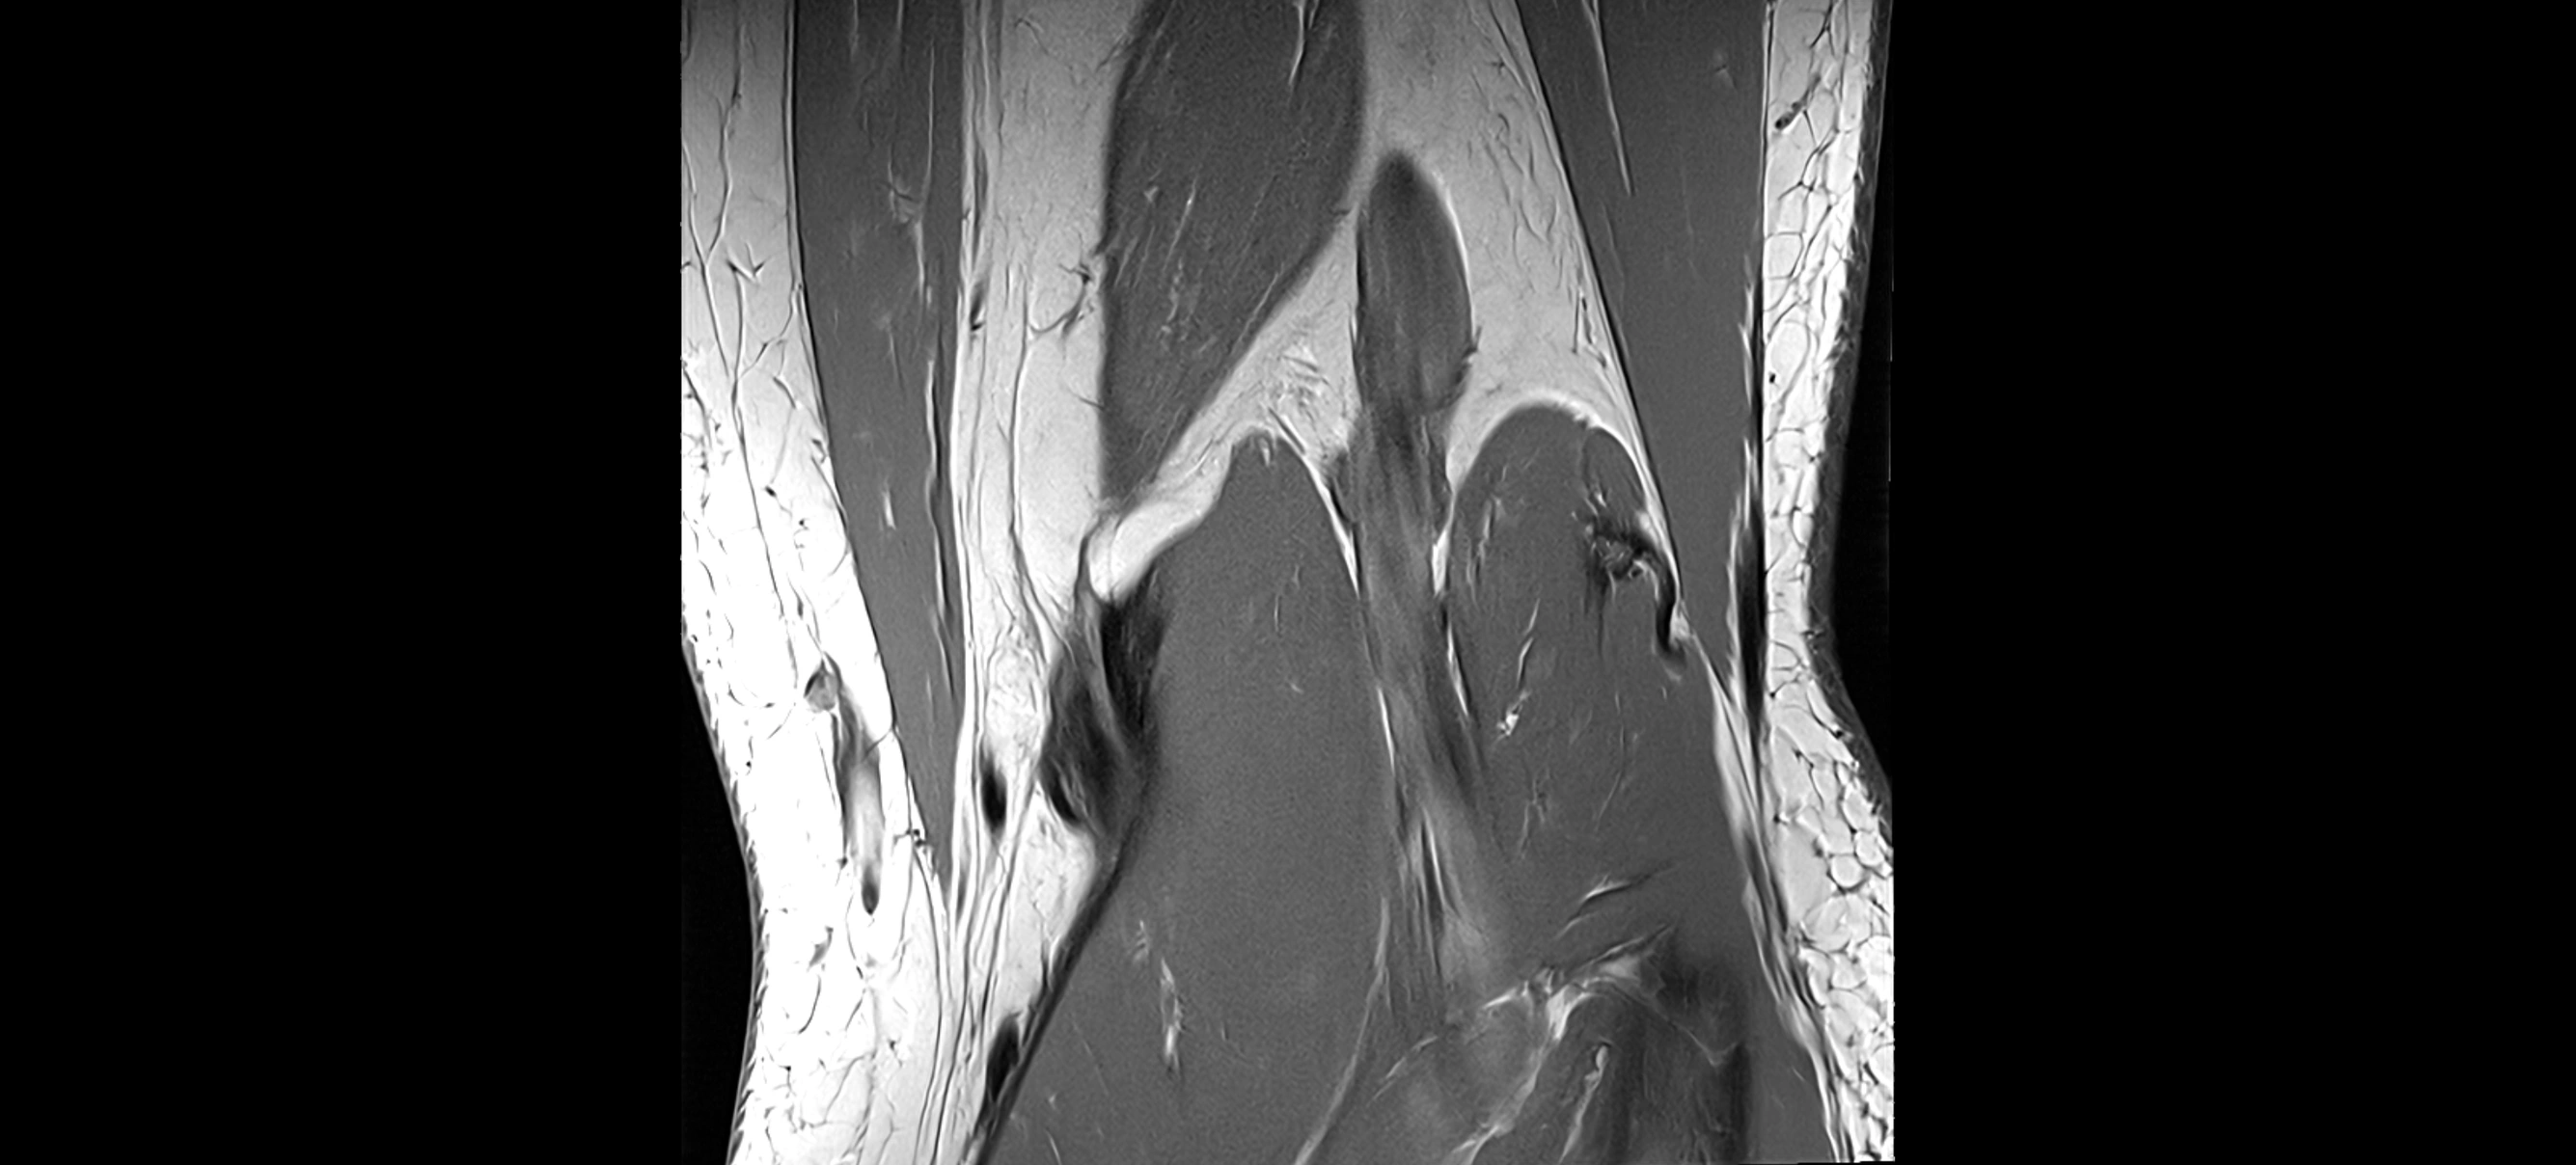

MRI images

image